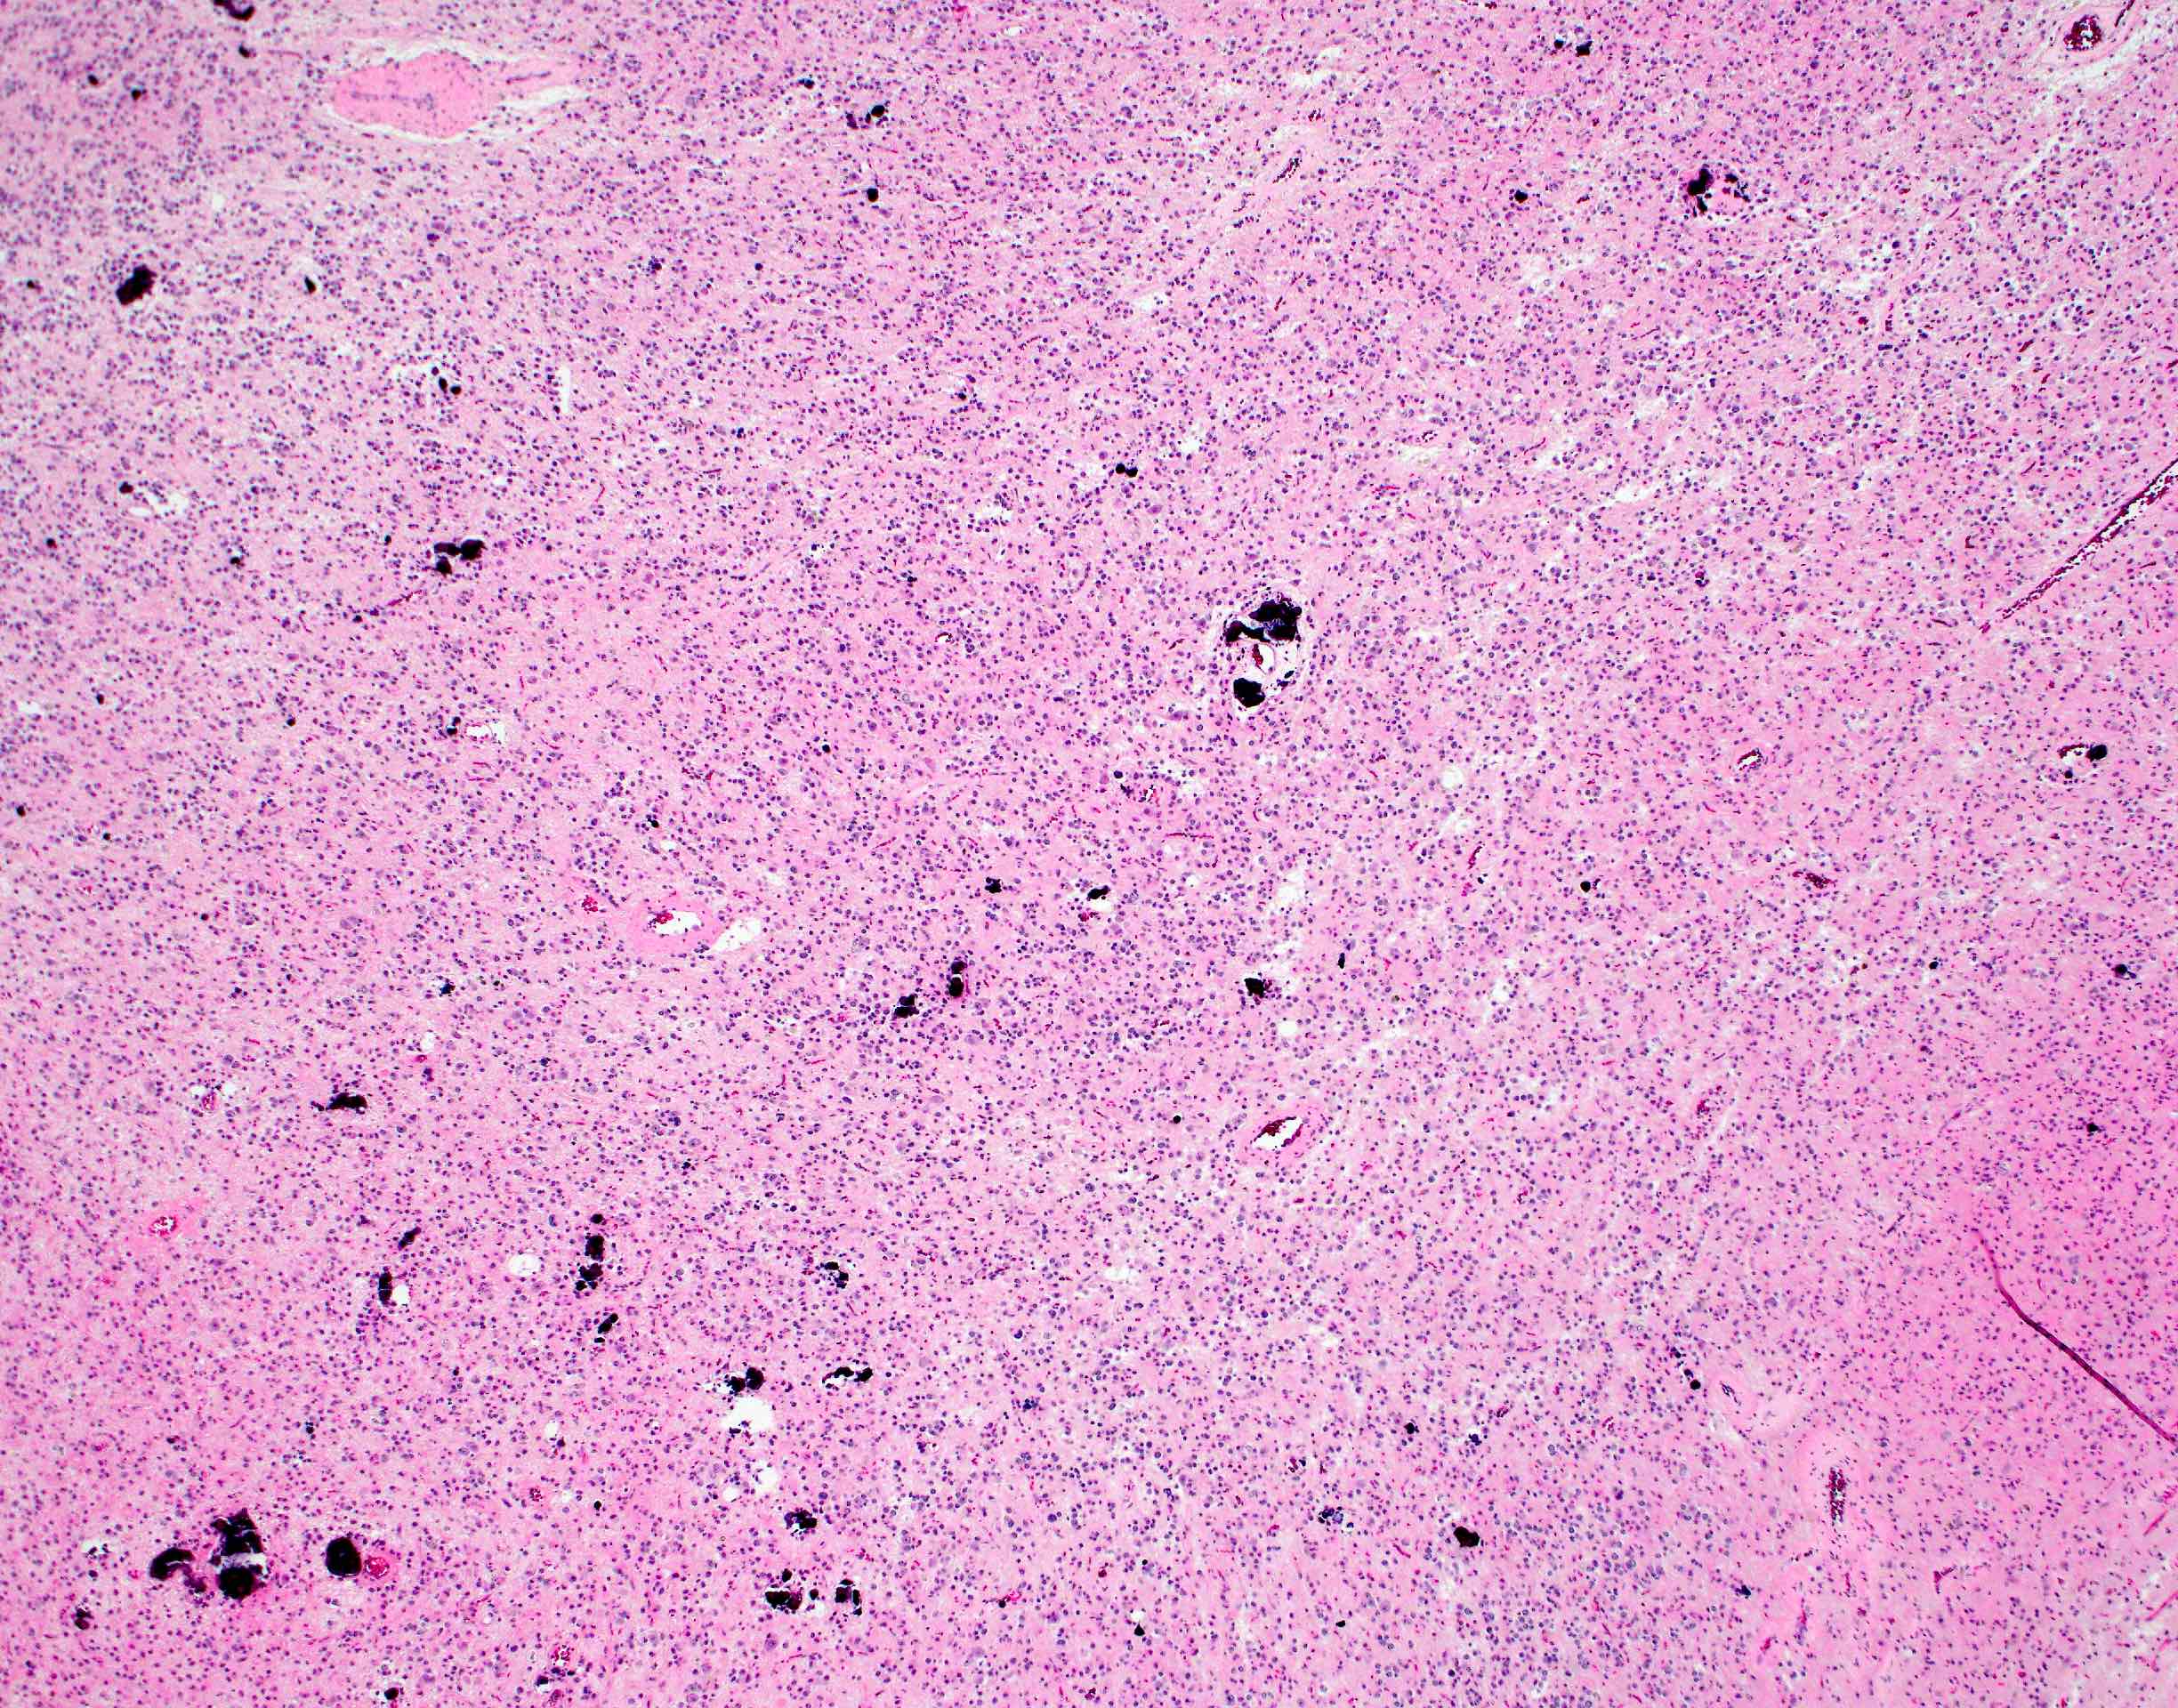

Microscopic (histologic) description

- Closely packed cells with small, round, monotonous nuclei (slightly larger than a normal oligodendrocyte)

- Perinuclear clearing (fried egg appearance)

- Formalin fixation artifact

- Will not be seen on frozen sections or smear preparations

- Network of thin walled, branching blood vessels (chicken wire vasculature)

- Microcalcifications (calcospherites) are characteristic

- Presence of perineural, perivascular or subpial aggregates of tumor cells (secondary structures of Scherer)

- Features of CNS WHO grade 3 oligodendroglioma:

- Presence of microvascular proliferation

- Presence of necrosis

- Presence of brisk mitotic activity

- Strict mitotic figure cutoffs do not currently exist; some authors suggest ≥ 6 mitoses per 10 high power fields for WHO grade 3 designation in tumors without necrosis or vascular proliferation (Neuro Oncol 2014;16:1244, Neuro Oncol 2016;18:888)

Microscopic (histologic) images

Contributed by Jared T. Ahrendsen, M.D., Ph.D. and John DeWitt, M.D., Ph.D.